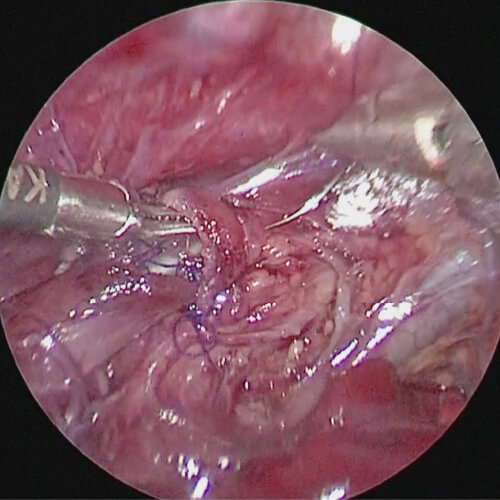

小児外科は心臓外科・脳外科・整形外科分野を除いた小児の一般外科であり、幅広い解剖学的知識が要求される診療科です。また、数100グラムの極低出生体重児から成人並の体重の中学生まで幅広い体格の子供を対象とするため、手術は繊細で正確な操作が要求される難しい科でもあります。当院においても既に、胸腔鏡下肺葉切除や胸腔鏡下縦隔腫瘍切除、腹腔鏡下後腹膜腫瘍切除、腹腔鏡下噴門形成、腹腔鏡下胆嚢摘出、腹腔鏡下先天性胆道拡張症手術、腹腔鏡下脾臓摘出、先天性食道閉鎖症や胎便性腹膜炎、小腸閉鎖症、横隔膜ヘルニア、鎖肛などの新生児手術、壊死性腸炎などの超低出生時体重児手術、胆道閉鎖症に対する葛西手術、ヒルシュスプルング病手術、肝芽腫や神経芽腫、横紋筋肉腫などの腫瘍全摘術、膵頭部腫瘍に対する膵頭十二指腸切除、正中頚嚢胞や側頚瘻などの頚部疾患手術、膵損傷治療など新生児から中学生までの高度な治療の実績が積まれています。